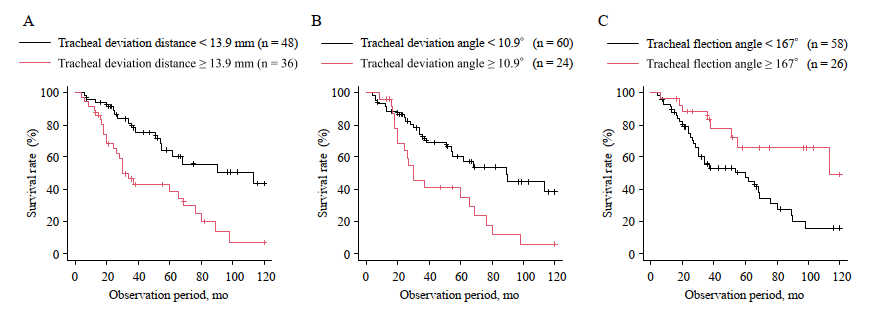

4) “どれくらい偏位しているか”も予後因子

ROC解析で生存に関連するカットオフを提示しています:

- 気管偏位距離 13.9 mm

- 気管偏位角 10.9°

- 気管屈曲角 167°(これ未満が不良)

そして多変量Coxで、気管偏位距離と気管屈曲角が独立した死亡予測因子になりました。

Figure 3